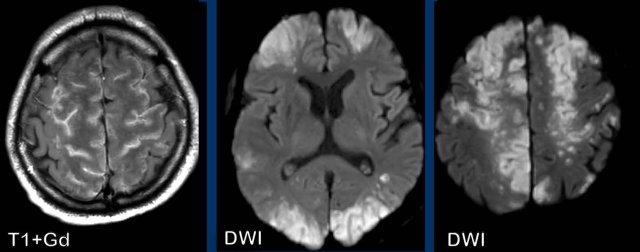

These four images are of a young patient with a pneumococal sepsis who deteriorated and became comatous.

Images

There are small enhancing nodules (yellow arrowheads) in the watershed areas and at the gray/white matter interface.

There is diffusion restriction (white arrowheads).

This pattern is identical to the previous cases.

Conclusion

This was regarded as septic emboli.